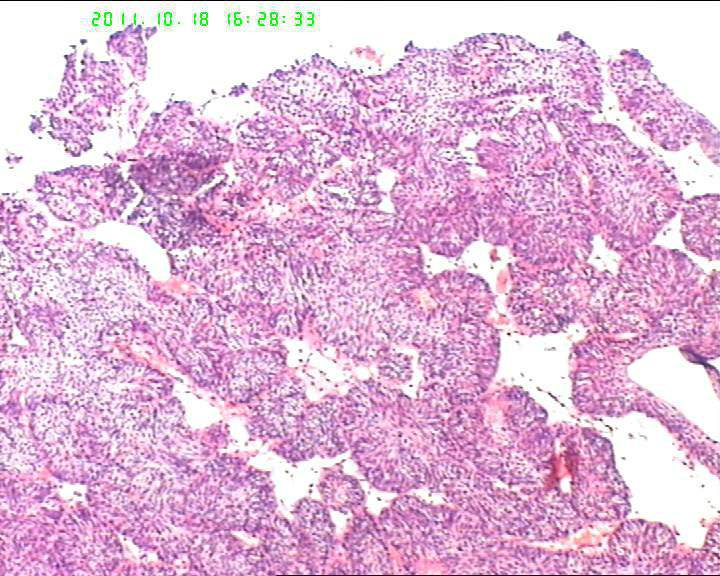

70岁女性体检发现膀胱肿物,是癌吗?

膀胱后壁一2*1cm大小肿物